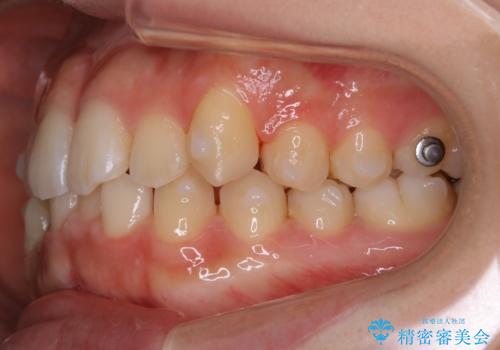

【非抜歯】すきっ歯と噛み合わせの治療

- 上の前歯のすきっ歯と下の前歯のガタつきを主訴にご来院されました。

噛み合わせの改善も同時に進めつつ、主訴の部分も効率的に治していくためマウスピース装置でゴムかけを行いながら治療を進めていきました。

正中離開(すきっ歯)

真ん中の歯が左右に開いてしまい隙間ができてしまう状態を「正中離開」といい、俗にすきっ歯と呼ばれています。

隙間を埋めていく方向に歯を移動させることで改善していくケースが多く、比較的治りやすい不正咬合のひとつとされています。

しかしながら、歯が捻じれていたり、噛み合う歯との位置関係によっては治療が難しくなる場合があります。